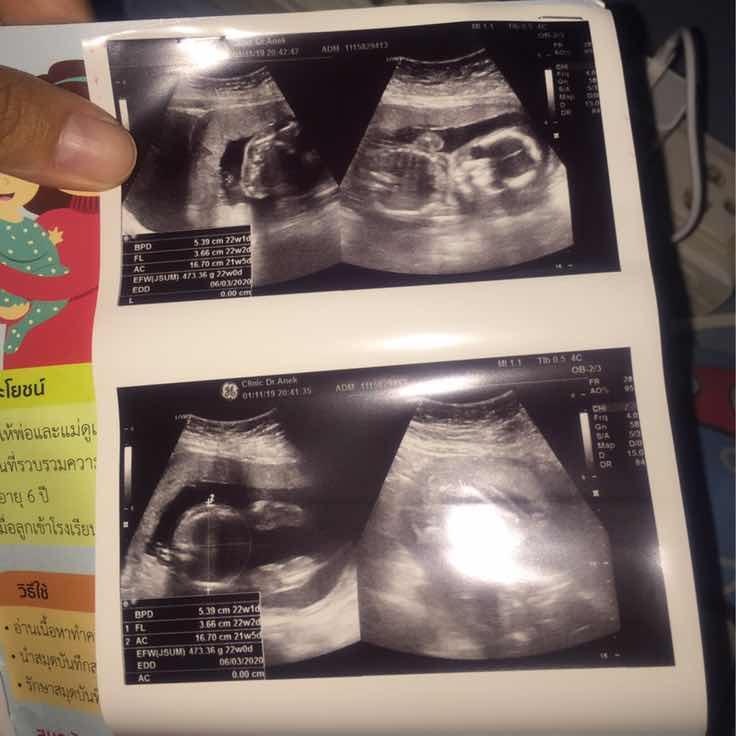

💕

22w

ซาว22wชัดมากค่ะ